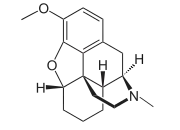

- Dimethylmorphine (6-O-Methylcodeine)

Dimethylmorphine Dimethylmorphine(6-O-Methylcodeine) |